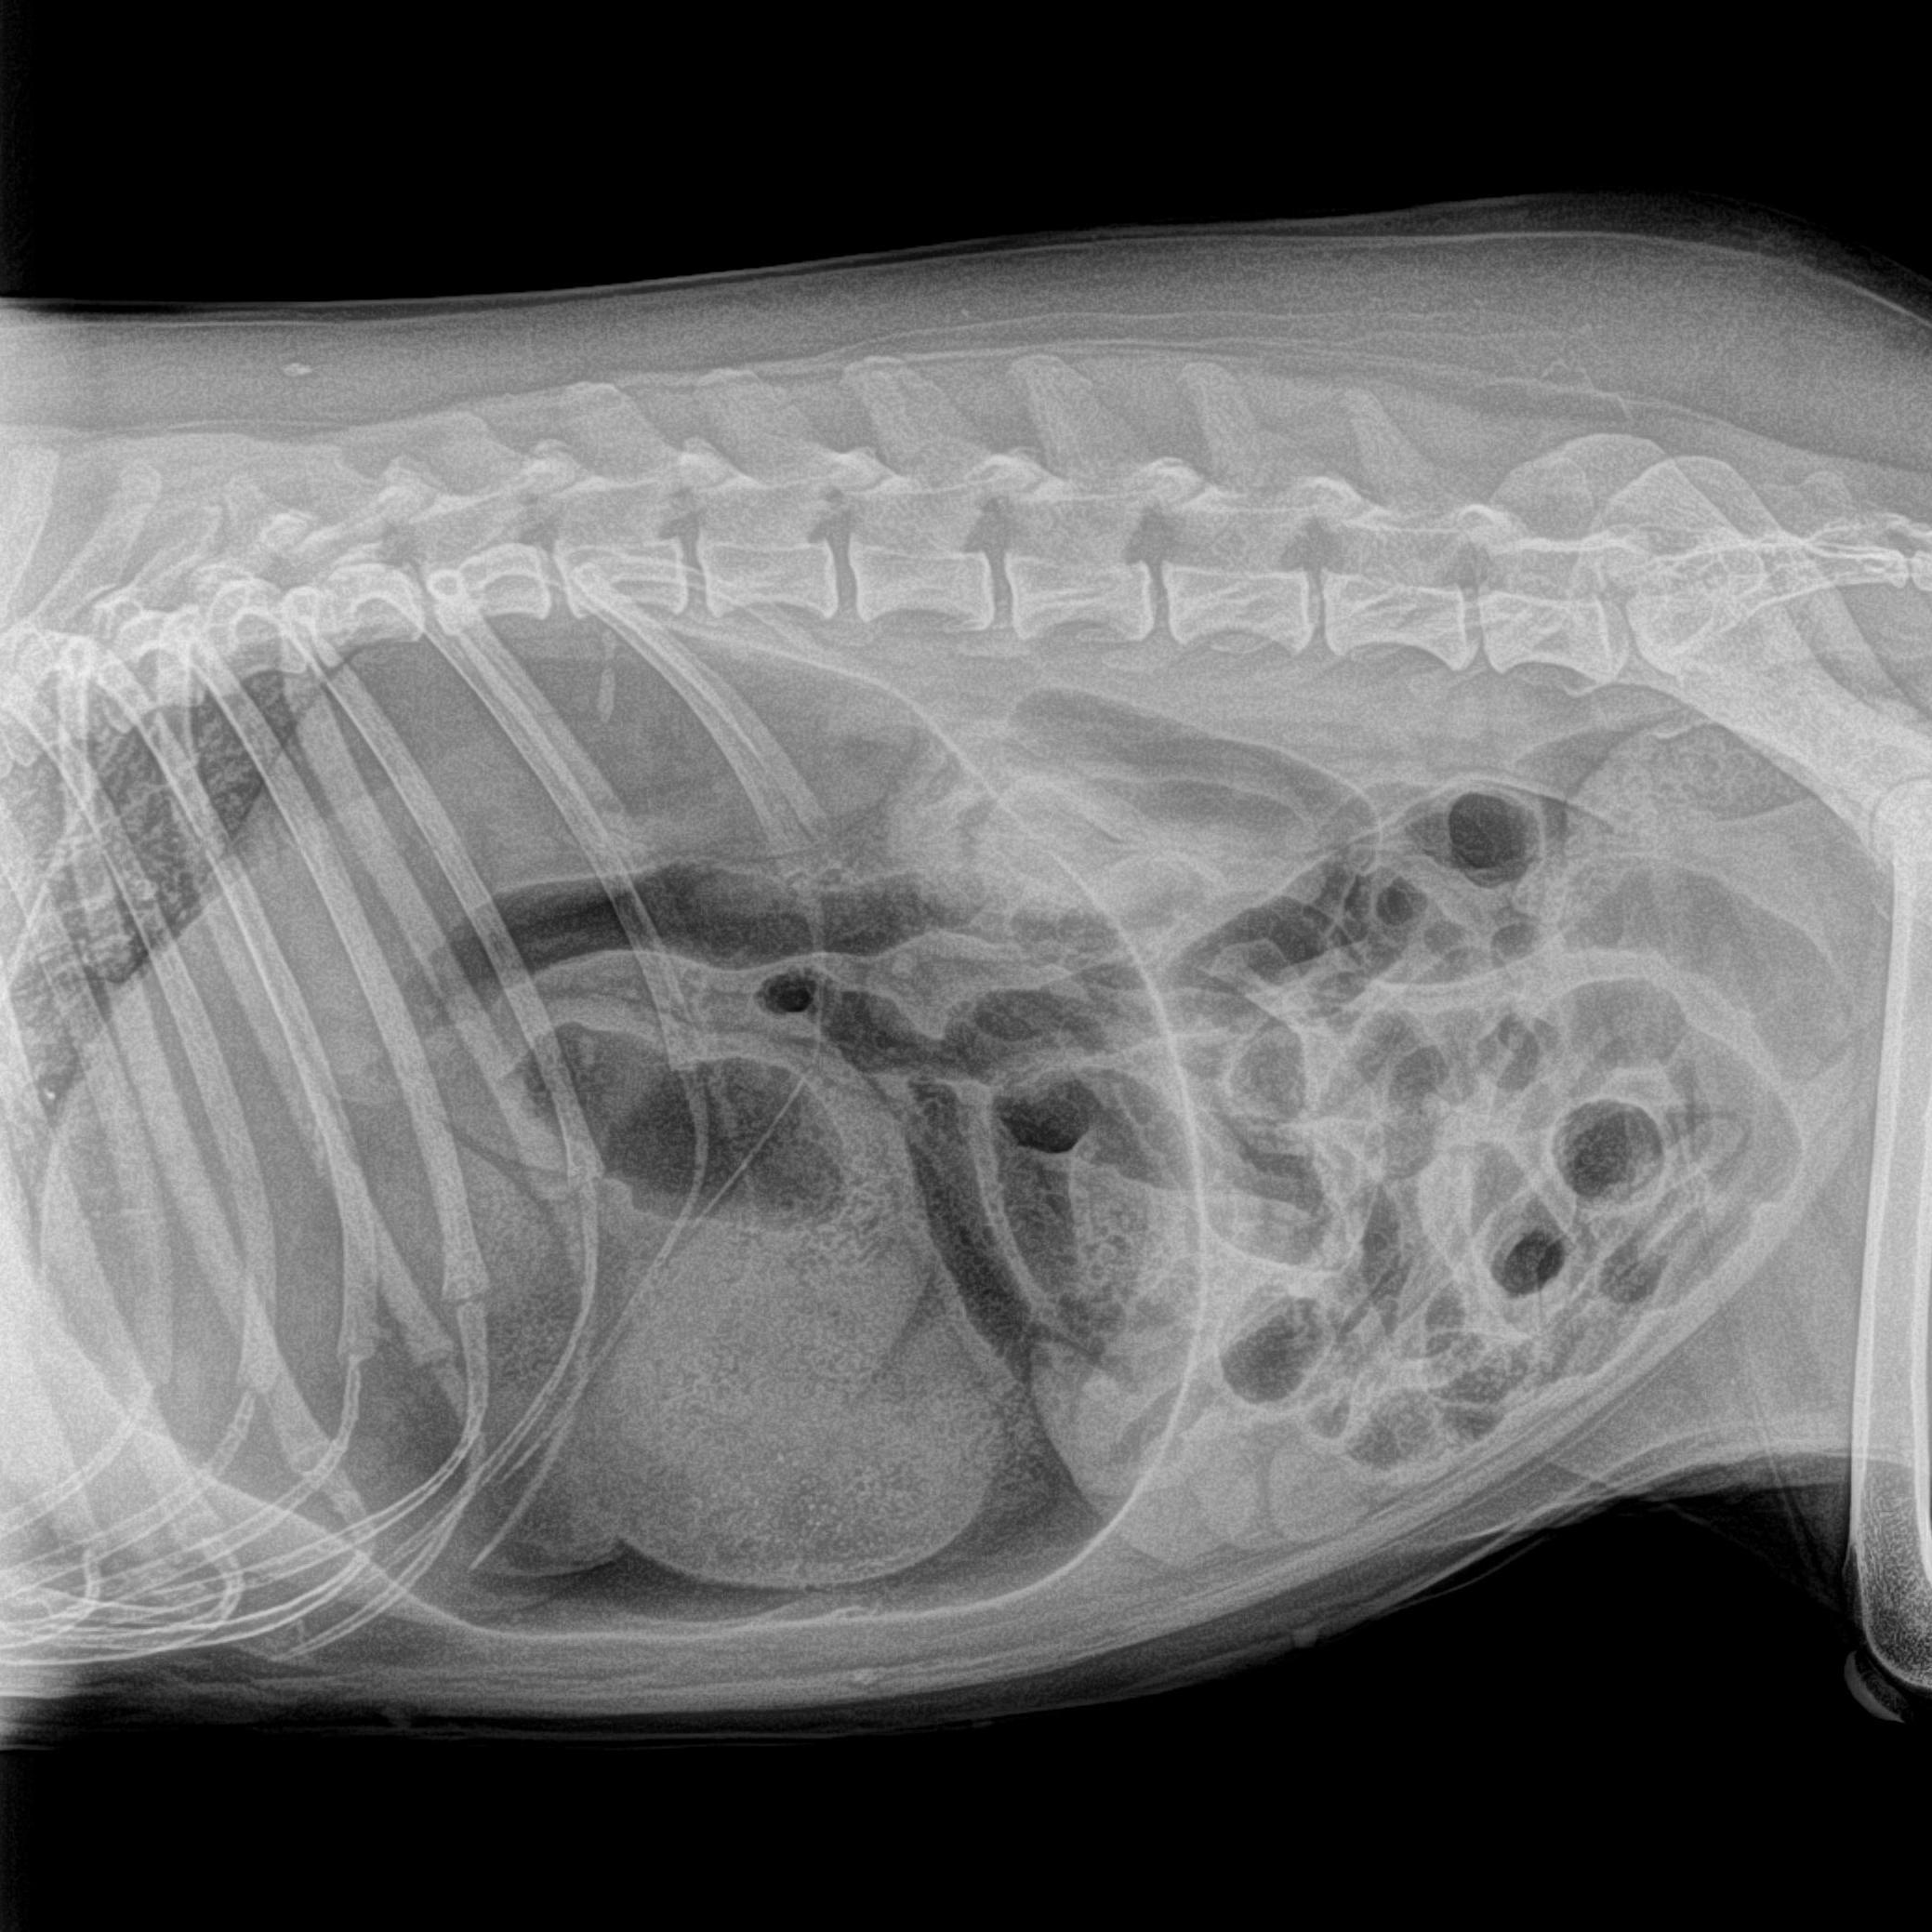

Radiographie abdominale

Elle permet de visualiser différents organes de l'abdomen. Elle est également utilisée pour la recherche par exemple de corps étrangers dans le tube digestif. Pour une meilleure visualisation de l'ensemble du tube digestif, il est parfois nécessaire d'utiliser des produits de contraste.

chienne gestante